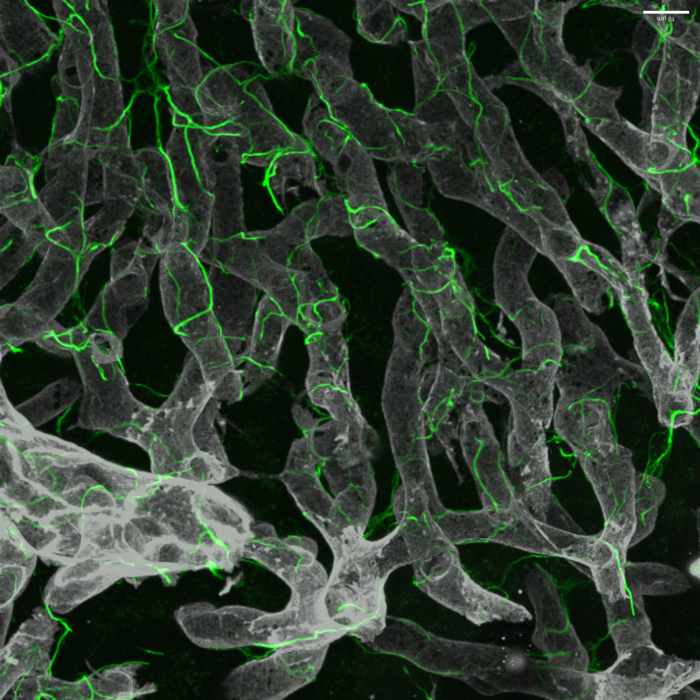

在健康的肝臟中,肝臟星狀細胞及其復雜的細胞投影(綠色)包裹在血管(灰色)周圍。 利用最新的技術——包括小鼠和人類肝組織的單核測序和先進的小鼠3D玻璃成像來表征關鍵的產生瘢痕的肝細